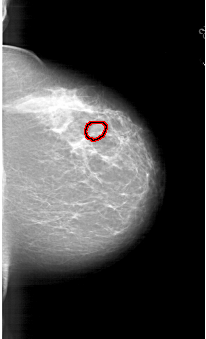

A_1767_1.LEFT_MLO

LEFT_MLO LINES 5821 PIXELS_PER_LINE 3736 BITS_PER_PIXEL 12 RESOLUTION 43.5 NON_OVERLAY

RIGHT_MLO LINES 5821 PIXELS_PER_LINE 3496 BITS_PER_PIXEL 12 RESOLUTION 43.5 OVERLAY

FILE: A_1767_1.RIGHT_MLO.OVERLAY

TOTAL_ABNORMALITIES 1

ABNORMALITY 1

LESION_TYPE MASS SHAPE OVAL MARGINS CIRCUMSCRIBED

ASSESSMENT 3

SUBTLETY 3

PATHOLOGY BENIGN

TOTAL_OUTLINES 1

BOUNDARY